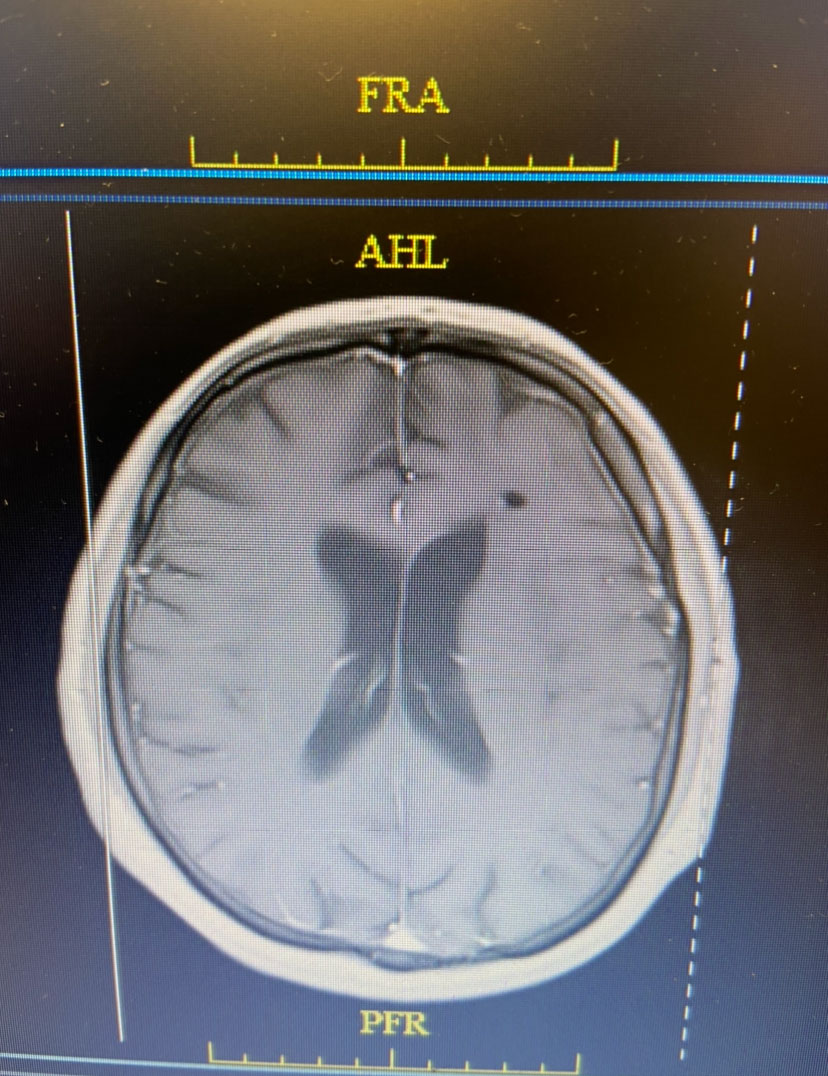

Because the lesion was sizeable, and causing much mass effect, and the diagnosis was unclear, and the patient was young with no other existing disease, it was decided to emergently bring the patient to the operating room for surgical removal of the mass. Surgery was performed by Dr. Michael Brisman. Stereotactic Brainlab navigation was utilized. A small left frontal craniotomy was performed. After making a small cortical incision, the Vycor transparent tubular retractor was inserted into the lesion. Thick yellow liquid was encountered under pressure consistent with frank purulence. (Image 2 shows intra-operative image of Vycor tubular retractor in deep left frontal mass with thick purulent material coming out under pressure.) Cultures were sent. The pus was fully washed out with gentle antibiotic irrigation.

Image 2: Intra-operative image of Vycor tubular retractor in deep left frontal mass with thick purulent material coming out under pressure.